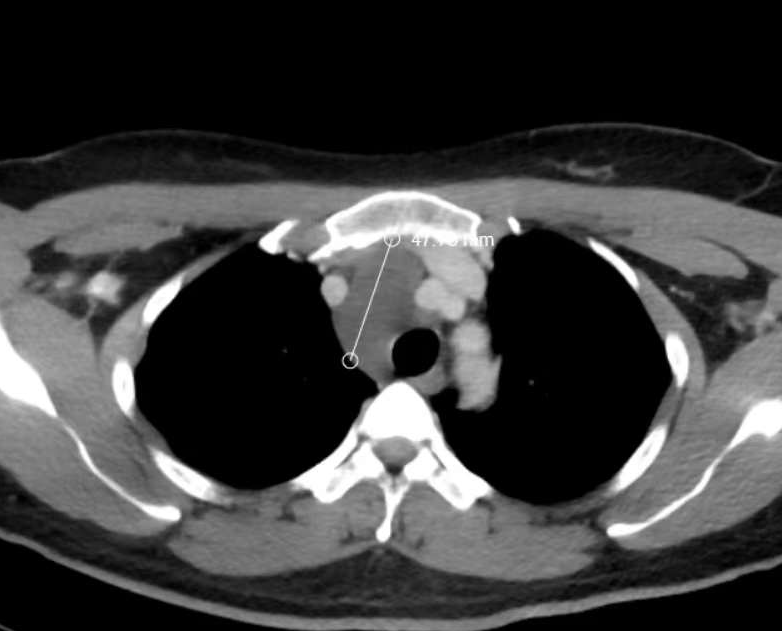

湘雅二医院驻桂胸外科专家梁恒星副主任医师仔细查看秦老师CT检查结果,详细询问秦老师相关病史后,宽慰他:虽然肿瘤范围比较大,有鸭蛋大小,但综合分析考虑该病变是良性病变的可能性大,可采用胸腔镜微创下切除占位病变。

位于大血管旁的纵隔病灶

虽然秦老师的病变极大可能是良性病变,但生长位置却极其“尴尬”——病灶紧邻人体最大的几根血管主动脉、无名动脉和上腔静脉,且病灶顶部紧挨喉返神经。微创手术操作稍有不慎,容易出现无法控制的大出血,或者损伤喉返神经造成声嘶,对秦老师日后的教师生涯产生无法估量的损失。

原来,在初步查看秦老师的CT后,梁恒星认为秦老师的病灶极有可能是一个充满液体的囊性病变。为此,他还组织了湘雅二医院驻桂放射科专家朱晖教授、神内科专家申向民教授一起商讨,最终明确——患者胸部磁共振提示患者病变为囊性,并且通过非创伤性血管成像技术提示颅内交通动脉良好,可以承受脑部血管一过性阻断的风险。